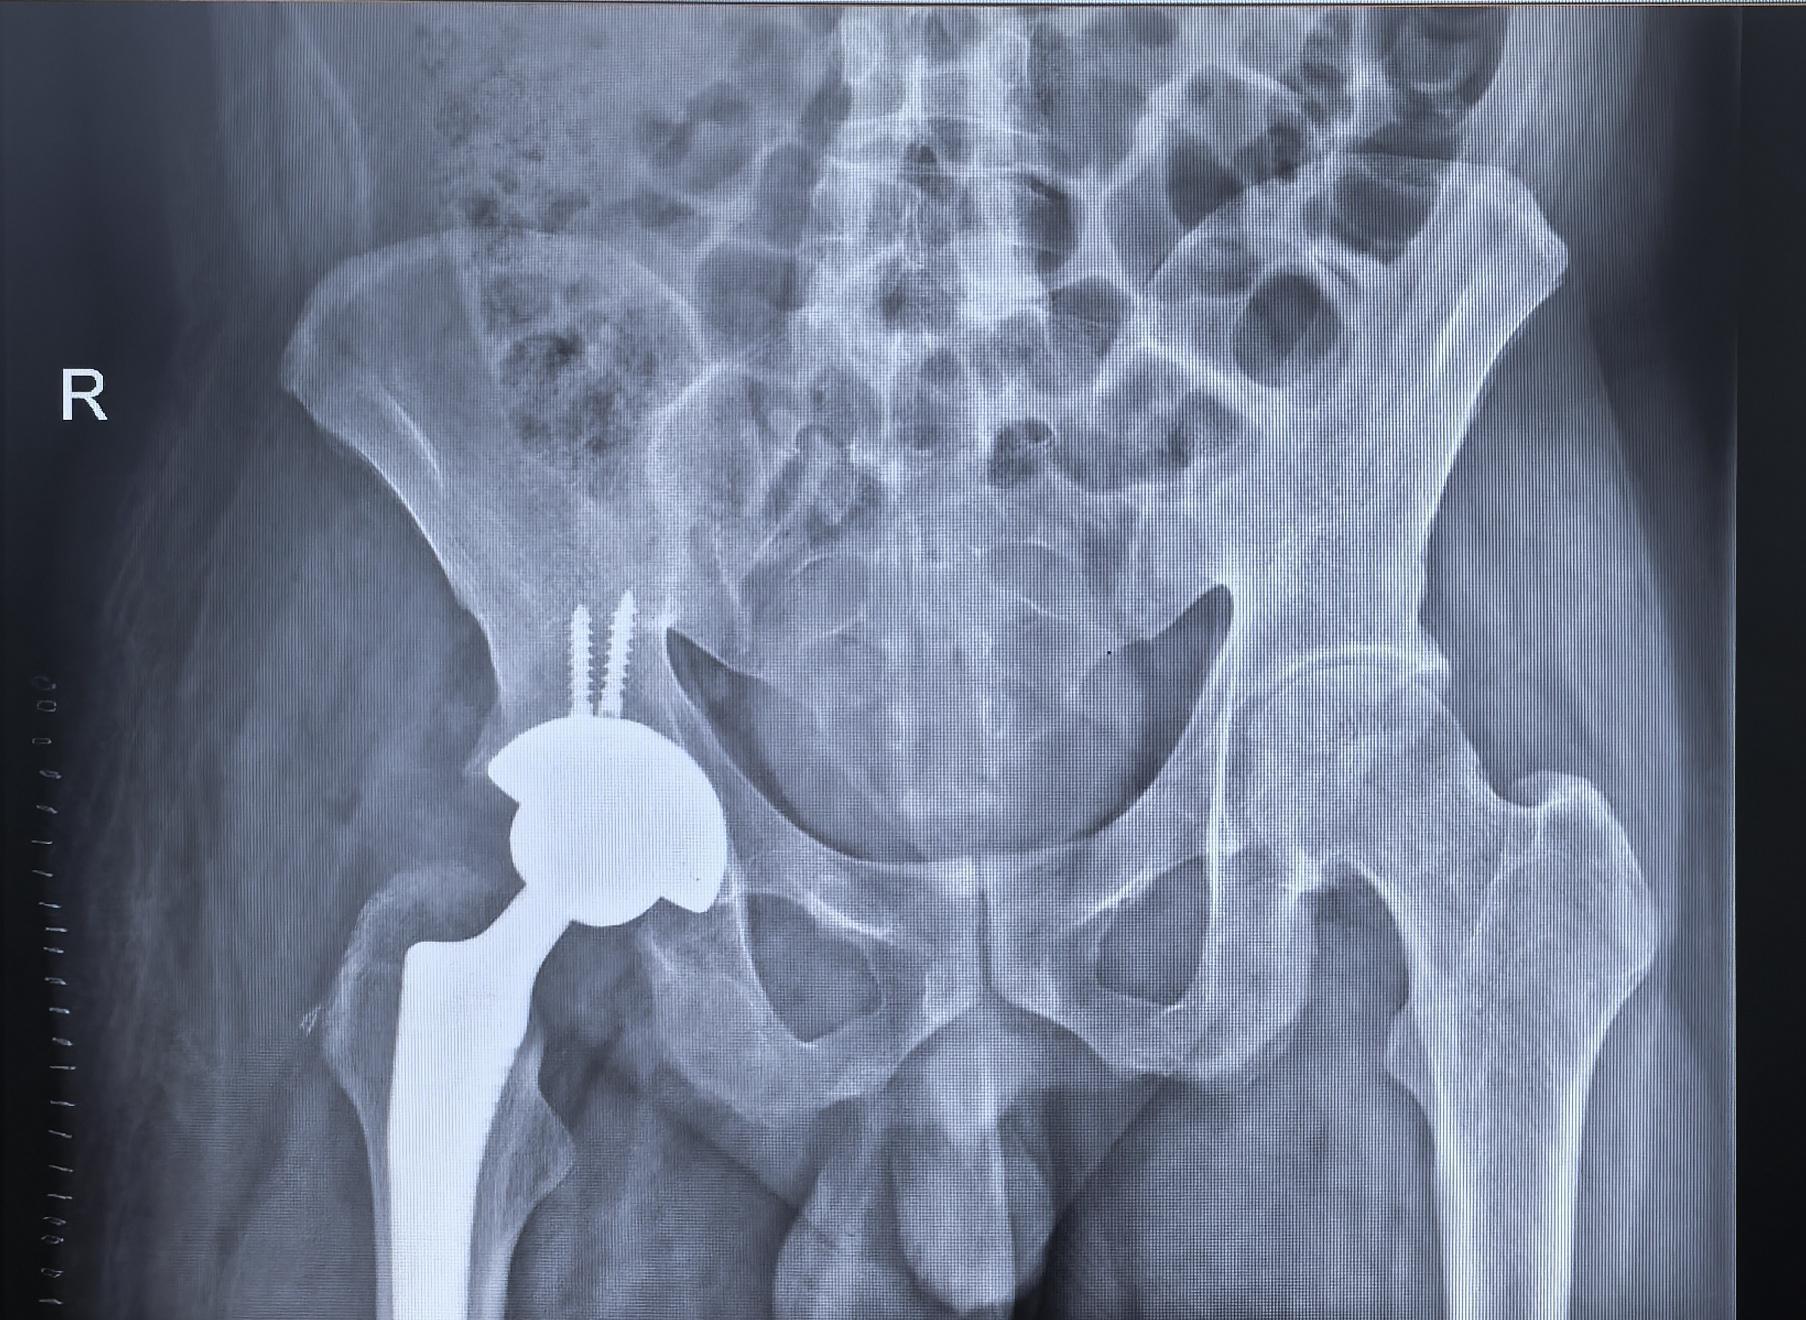

强直髋。强直髋,髋关节无活动度,如有条件,尽早手术,拖得越久,软组织越挛缩,肌肉纤维化越明显,康复起来也就越困难。